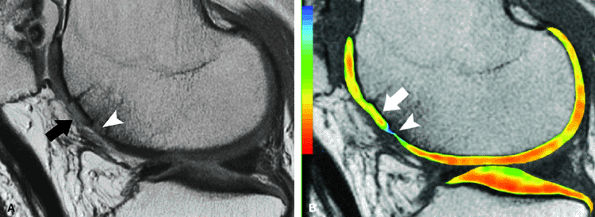

FIGURE 7.30 ● Sagittal inversion recovery (A) and fast spin-echo (B) MR images of the knee in a 36-year-old patient performed 1 year following fresh-frozen allograft transplantation in the medial femoral condyle. The allograft is slightly proud with persistent bone marrow edema pattern, both within the graft and at the graft-host interface, associated with mild subchondral collapse (black arrow in B). Corresponding inversion recovery (C) and fast spin-echo (D) MR images obtained a year and a half later, with interval tibial osteotomy, demonstrate further collapse of the allograft bone, with the areas suspicious for the presence of nonviable bone (white arrow), which is of low signal intensity on both pulse sequences. Note also the fluid imbibition (arrowhead in D) beneath the graft subchondral plate.

|